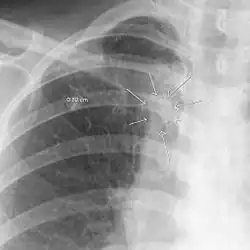

| The arrows denote an ill-defined nodular opacity in medial aspect of right upper lobe with ill-defined rim of lucency surrounding it | |

In radiology, the air crescent sign (also called the Monad sign[1]) is a finding on chest radiograph and computed tomography that is crescenteric and radiolucent, due to a lung cavity that is filled with air and has a round radiopaque mass.[2] Classically, it is due to an aspergilloma, a form of aspergillosis, that occurs when the fungus Aspergillus grows in a cavity in the lung.[3]